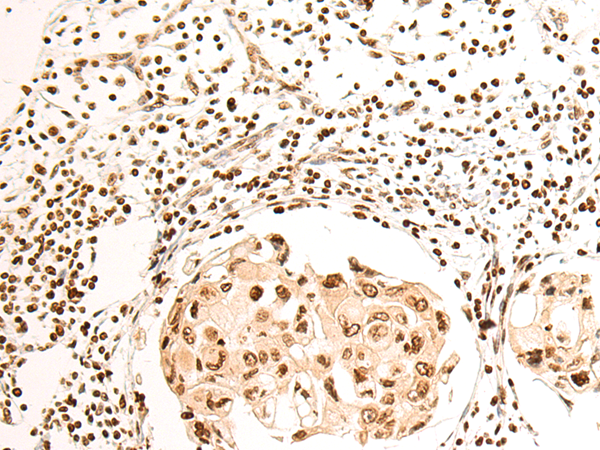

IHC positive control: |

Human breast cancer and Human prostate cancer |

IHC Recommend dilution: |

50-200 |